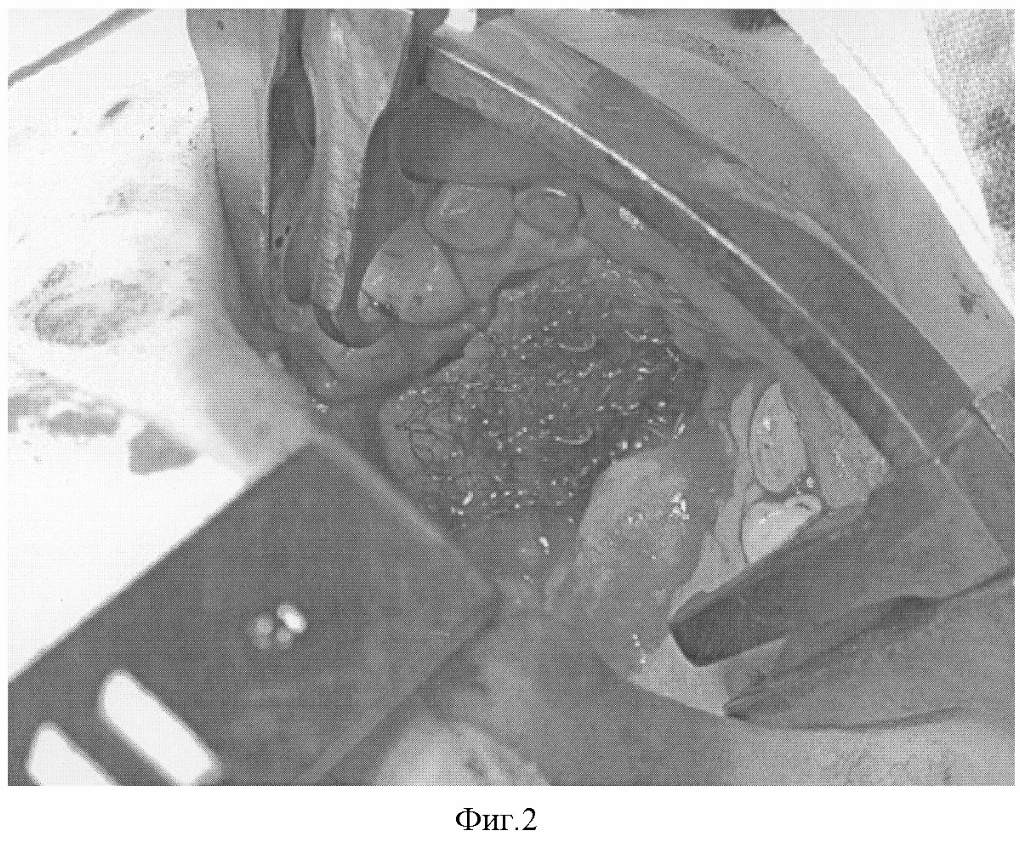

Пример. Больной Д., 5,5 лет, обратился в клинику по поводу послеоперационного дефекта среднего и переднего отдела твердого неба. Ранее оперирован по поводу врожденной полной правосторонней расщелины твердого и мягкого неба, дважды – по поводу послеоперационного дефекта твердого неба (фиг.1). Под эндотрахеальным наркозом выкроены трапециевидные слизисто-надкостничные лоскуты по обе стороны дефекта, которые мобилизованы, ротированы в сторону носовой полости, нижний лоскут деэпителизирован, на раневую поверхность верхнего лоскута (фиг.2) и деэпителизированную поверхность нижнего установлены сетчатые имплантаты с размерами ячейки от 4×4 мм, изготовленные в соответствии с их конфигурацией из никелид-титановой нити, толщиной 60 мкм, верхним рядом узловых швов имплантаты фиксированы между собой, нижним – мягкие ткани, дополнительная фиксация осуществлена йодоформными полосками и съемной защитной пластинкой. Послеоперационное течение гладкое, швы сняты спустя 10 суток. Заживление ран – первичное (фиг.3). Рекомендовано наблюдение у ортодонта и лечение у логопеда. При осмотре через 6 месяцев отмечены хорошие анатомические и функциональные результаты.